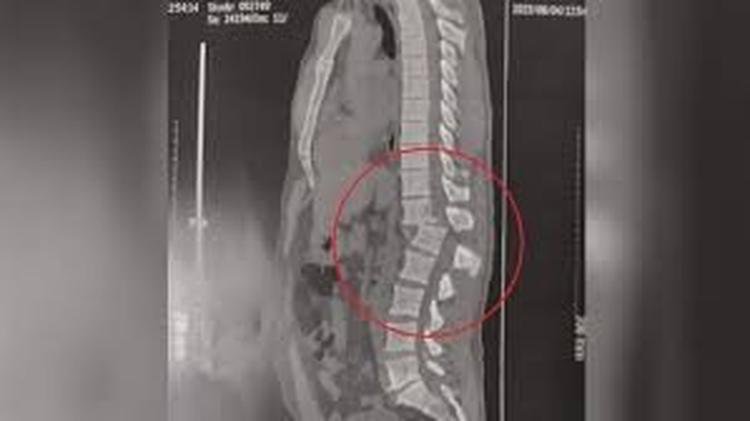

A lesão foi entre as vértebras T12 (fim da parte torácica) e L1 (início da parte lombar). A vértebra inferior (L1) se deslocou para trás em relação à vértebra superior (T12).

Segundo Daniel Oliveira, ortopedista especializado em coluna vertebral e diretor do NOT - Núcleo de Ortopedia e Traumatologia de Belo Horizonte, a lesão de Regilânio pode ser considerada delicada, grave e a mais complexa da coluna toracolombar porque houve uma rotação e torção da medula.

O ortopedista explica que, para esse tipo de lesão é realizada uma cirurgia onde se colocam pinos e parafusos metálicos de titânio para a redução da fratura, alinhamento ósseo e descompressão medular.

De acordo com o médico que realizou a cirurgia, João Ananias, foi colocada uma haste na parte posterior da coluna, pegando vértebras acima (3) e abaixo do local do trauma (3), afixada com 12 parafusos metálicos de titânio e uma haste.